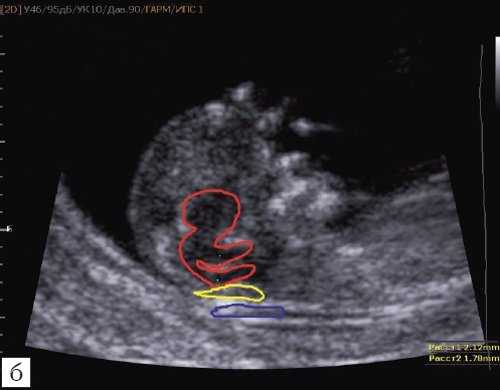

Так как речь идет о сроках первого скрининга, т.е. раннего осмотра, новый ультразвуковой маркер мы назвали "осьминожкой" (рис. 3).

а) Стрелками указана голова "осьминожки" - диэнцефалон (таламус).

б) Красный цвет - диэнцефалон (таламус), со стволом мозга (верхняя ножка) и IV желудочком (нижняя ножка); желтый цвет - большая цистерна головного мозга; синий цвет - воротниковое пространство.